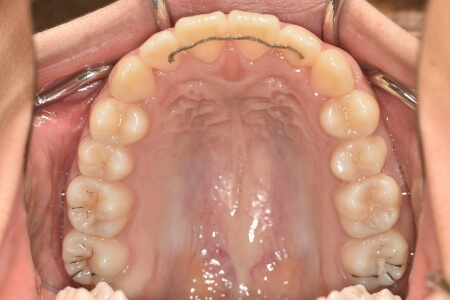

開咬(非抜歯)【2137】

初診時

症例 症例 症例 症例 症例

治療内容の詳細 初診時15歳の女性で、上の歯のがたつき、かみ合わせ、歯の中心のズレ、鼻から下が長いのを気にされ来院されました。

検査の結果、上顎前歯部叢生および開咬を伴うアングルⅠ級不正咬合と診断しました。

治療としては、非抜歯の上、マウスピース型矯正装置(インビザライン)で配列を行いました。顎間ゴムの協力もあり、開咬、中心のズレがきれいに改善されました。